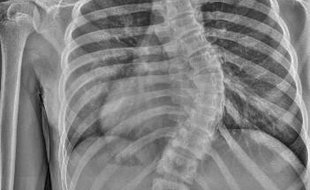

Náš tým operatérů z oddělení chirurgie páteře dostal v minulých dnech příležitost vyzkoušet v praxi nový páteřní systém, který splňuje nejpokrokovější požadavky korekce páteře a nabízí dosud nejmodernější způsob řešení dětské skoliózy. Naši lékaři operovali pomocí tohoto systému dvě dívky ve věku 13 a 14 let. U obou se zcela zásadně podařilo nejen srovnat páteř, ale i vrátit zrotované obratle do správného postavení, a odstranit tak nechtěné kosmetické deformity.

Srovnáním a navrácením zrotované páteře do správné polohy dochází k odstranění kosmetické deformity. Tou je nejčastěji hrb nebo asymetrie prsou u dívek. Dalšími přednostmi uvedeného systému jsou podle karvinských lékařů snadnější manipulace a méně šroubování.